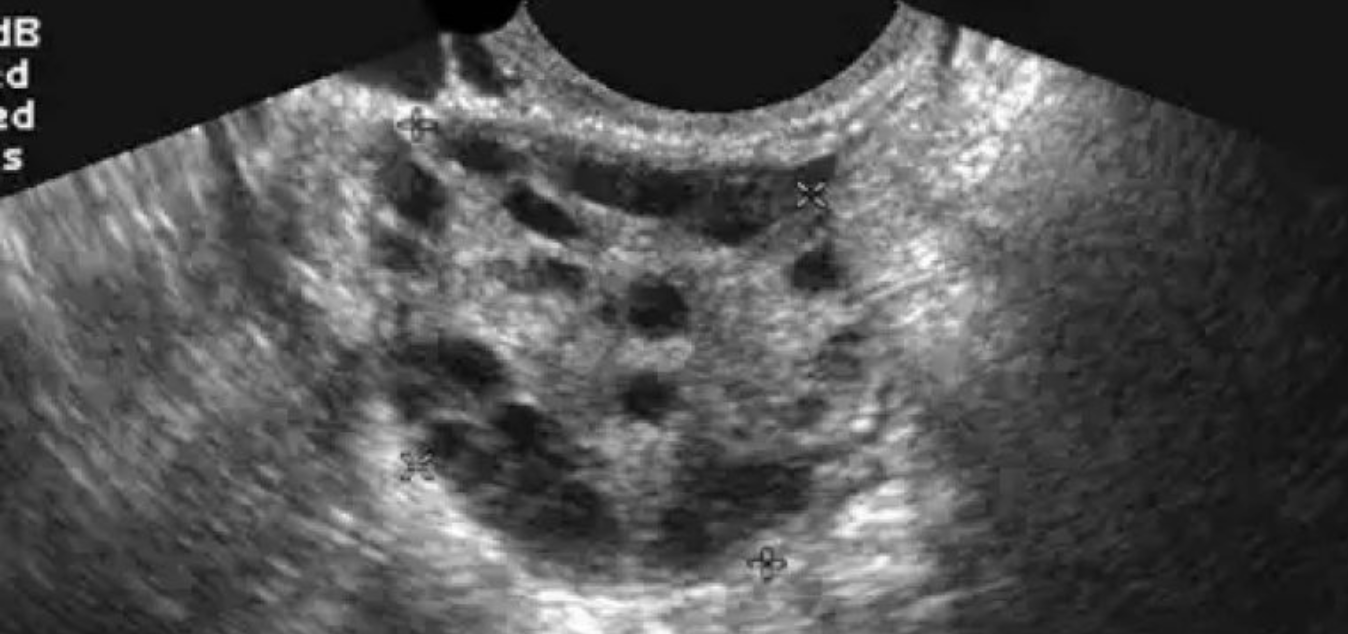

El Sindrome de Ovario Poliquístico (SOP) es una patología muy común entre las mujeres en edad fértil. Tan solo en los Estados Unidos, se calcula que el SOP afecta a una de cada 10 mujeres, de acuerdo con el Departamento de Salud y Servicios Humanos del país del norte.

Las mujeres que sufren de SOP tienen un desequilibrio hormonal y problemas metabólicos que pueden afectar su salud y aspecto general. El SOP también es una causa común de infertilidad que se puede tratar.

El SOP se presenta con mayor frecuencia entre los 18 a 36 años; sin embargo, en la vida adulta la mujer deberá extremar la vigilancia, ya que se ha observado que este trastorno es un aviso de que está en riesgo de desarrollar diabetes y enfermedad cardiovascular secundaria a trastornos metabólicos